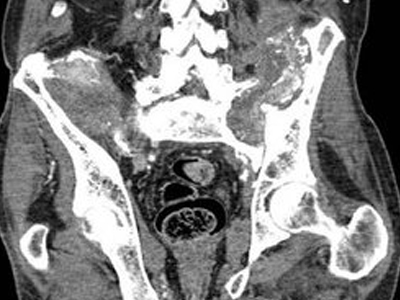

骨膜反应图 (51)

骨膜反应图 (50)

骨膜反应图 (49)

骨膜反应图 (48)

骨膜反应图 (47)